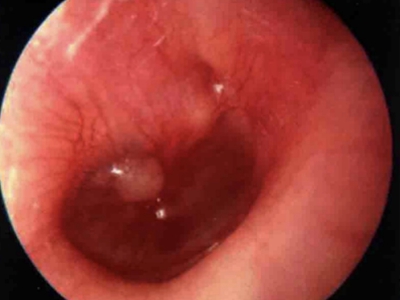

鼓膜炎又称为大疱性鼓膜炎,是鼓膜和邻近鼓膜的外耳道皮肤的急性炎症。由病毒感染所致,多发生在儿童和青年人,多为单侧,冬季多见。根据有感冒史、耳痛的症状及检查所见,容易诊断。

鼓膜炎的首发症状为外耳道剧痛,并可有轻度听力下降。随后,由于大疱破裂而有稀薄血性分泌物从外耳道流出;由于病变限于鼓膜的上皮层,未波及纤维层,故大疱破裂后无鼓膜穿孔。